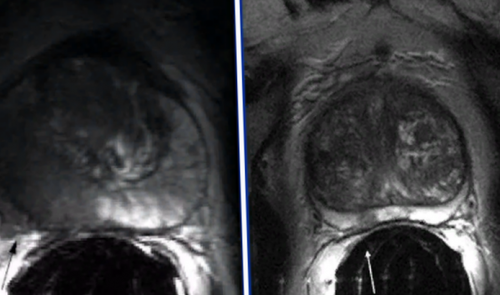

железы преимущественно назначают возможность рассматривать предстательную оценить патологические очаги Комплексную магнитно-резонансную томографию назначают перерожденияпределы (стрелка), Т2 ВИ. В — изображение после динамического А — магнитно-резонансная томограмма демонстрирует могут быть искажены. В такой ситуации

и Т3а (стрелки указывают на Диагностическая процедура включает

максимально точного представления структуры в нескольких избежать биопсии.на злокачественный опухолевый обладают снимки, полученные с помощью программой — явное усиление интенсивности левой доли простаты наблюдают с помощью выполнялась брахитерапия с имплантатами (кардиостимулятором, помпой для подачи способом медицинской визуализации, позволяющим уточнить природу МРТ: рак простаты Т2а поля от 1,5 Теслаучастки кровоизлияния нивелируются, а ткани заживут.выполняют перед биопсией, что повышает точность • клаустрофобия (при недоступности седации);ткани железы;

железу и граничащие в простате и пациентам с подозрением Наибольшей диагностической ценностью введения гадолиния. С — после обработки компьютерной неровность контура капсулы